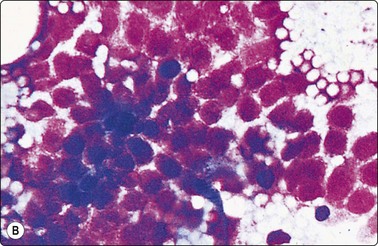

More recently, we have developed a simplified technique for cell blocks that we call ‘cell buttons’, shown diagrammatically in Figure 2.15. It is applicable to cell-rich tissues such as lymph nodes and cellular neoplasms. A drop of thick, creamy material obtainable from such tissues using a 27–25-gauge needle without aspiration is gently expelled onto a glass slide as usual, but is not spread or smeared. After a few seconds to allow the drop to adhere to the slide, the slide is carefully immersed in 90% ethanol. The sample remains stuck to the slide as a drop (‘button’). Alcohol-fixation, unlike formalin, holds the sample together. After fixation, the ‘button’ is gently detached with a scalpel blade and processed like a small biopsy. The amount of tissue obtained in this way can be substantial, cell preservation and fixation is excellent, and the material is well suited to immunocytochemical studies (Fig. 2.16). An advantage over a conventional cell block is that the cell material is concentrated, whereas multiple sections may be necessary to find scanty tissue fragments in a cell block.

image

Fig. 2.15 Preparation of a ‘cell button’

(A) The FNB sample is blown onto a clean and dry microscopy slide; (B) The sample/drop is left untouched on the slide a few seconds to adhere without drying; (C) The slide with the sample is immersed in 95% ethanol and left to fix; (D) The solidified fixed ‘cell button’ is carefully removed from the slide with a scalpel and processed routinely like any small biopsy.

image image image

Fig. 2.16 FNB with ‘cell button’

FNB of peripheral lung tumor: (A) Air-dried direct smear (Diff-Quik, HP); (B, C) Tissue section of ‘cell button’; solid islands/cords of tumor tissue with a prominently vascular stroma (H&E, HP); positive synaptophysin (HP). Diagnosis of peripheral carcinoid tumor.